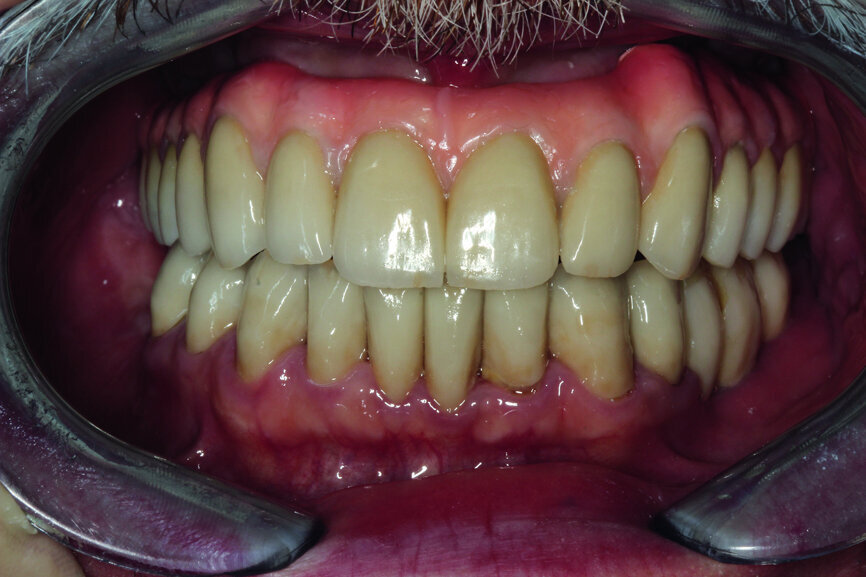

Fig. 15: Test of the construction together with crowns and the mouth slightly open.

After the model was analysed, we proceeded to analyse the fitting and the aesthetics in the mouth of the patient. Carrying out such a test makes a lot of sense, especially in a dynamic way, and by asking the patient to make various facial movements, such as smiles and grimaces, we can assess the properties of the course of the border line of the zenith of the teeth and the transition into a gingival garland. It is of real importance as at this stage that we can plan the process of covering the construction with pink porcelain or composite (Figs. 15–17).